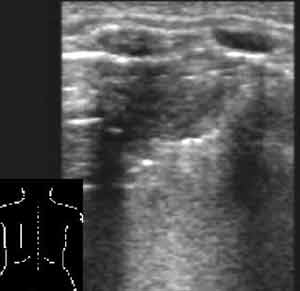

Рис. 5. То же, что на Рис. 4, во взаимно перпендикулярной плоскости.